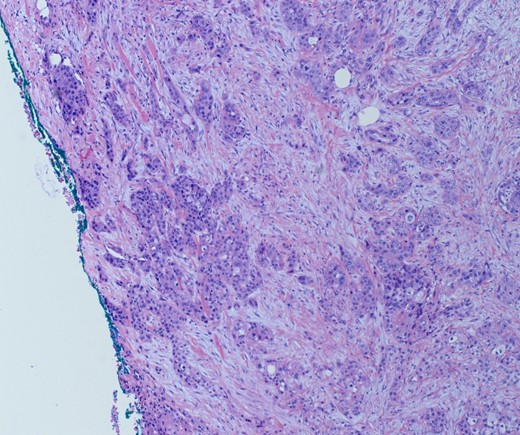

She underwent an open pylorus-preserving pancreatoduodenectomy with segmental superior mesenteric vein resection with primary reconstruction (ISGPS Type 3) without complication. Final pathology demonstrated a 3.6-cm poorly differentiated adenosquamous carcinoma with SMV invasion into the intima (Fig. 2), 1 of 24 regional lymph nodes with metastatic carcinoma, lymphovascular and perineural invasion (Fig. 3), and an 85% squamous differentiation (Fig. 4). There was a partial pathologic response (College of American Pathologist Grade 2) within the primary tumor and involved lymph node tumor [7]. There was noted to be tumor extension within 1 mm of the superior mesenteric artery margin (Fig. 5) (R1 status) with negative additional margins. She recovered without complications and was discharged home on the fourth post-operative day. Repeat staging CT imaging demonstrated no evident disease. She was initiated on adjuvant systemic therapy.

Adenosqumous carcinoma with both components (adeno and squamous) A19 Cytokeratin 7 immunostain, highlighting the adenocarcinoma, and p40 immunostain, highlighting the squamous carcinoma component